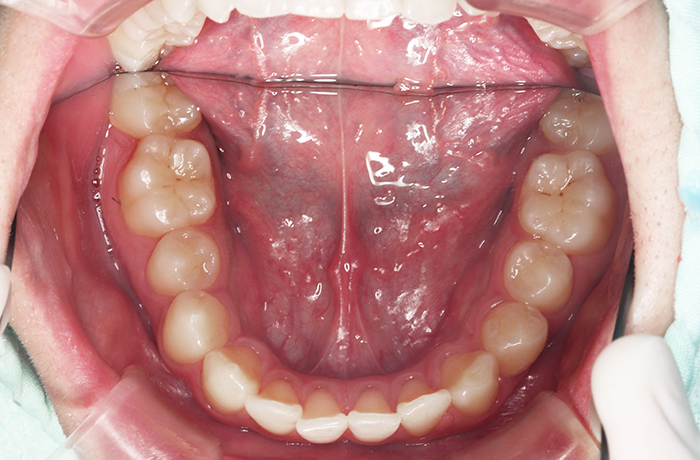

T様

治療前

年齢 28歳

性別 女性

治療名称 唇側ブラケット装置(ワイヤー矯正)

総額治療費用 880,000円(税込10%) 金額備考 精密検査料・診断料 33,000円(税込10%)

治療期間 2年6か月 通院頻度など 1か月ごと

治療内容

患者の症状 叢生、上下顎前突

治療方法 上下顎小臼歯の4本抜歯して唇側マルチブラケット装置にて矯正

治療結果 叢生の解消、口元の突出感も緩和され咬み合わせが良くなりました。

※治療結果は患者様によって個人差があります。

その他治療に関する情報 装置撤去までの通院回数は23回、その後の保定期間(2年間)は3か月に1度の通院。

治療を行う上での注意点

リスク/副作用 治療前に親知らずの抜歯が必要な場合があります。